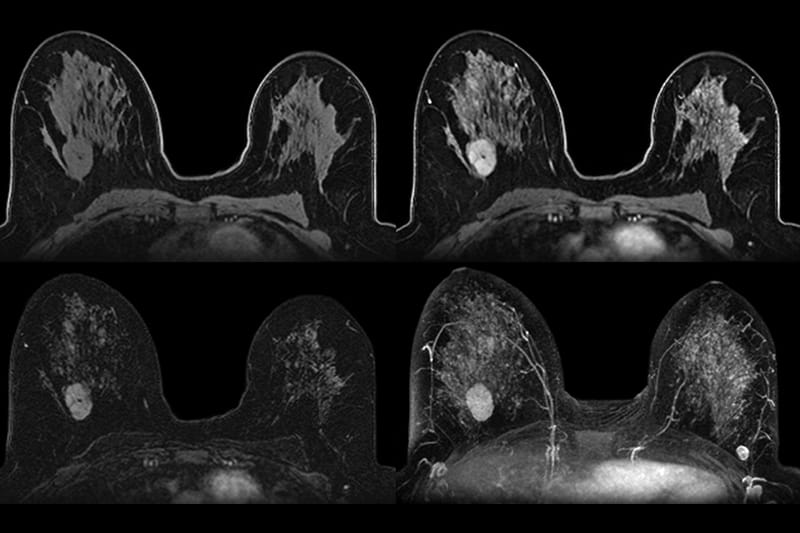

A high-resolution, radiation-free scan that offers the most sensitive screening for early breast cancer detection, especially in women with dense breast tissue or elevated risk.

Your mammogram might not tell the full story. Breast MRI uses powerful magnetic fields, not radiation, to create detailed, 3D images of your breast tissue. It’s the most advanced tool available for detecting cancer that might be missed by traditional screening, giving you clarity and confidence about your breast health.

You’ll lie face down on a comfortable padded table as a contrast agent is delivered through a small IV. This helps highlight abnormal tissue. The scanner uses magnetic fields (no radiation) to generate high-resolution, cross-sectional images of your breasts.

Step 2: Precision Imaging for High-Risk and Dense Tissue

Breast MRI can detect tumors as small as a few millimeters and is especially useful for women with dense breasts, BRCA mutations, family history of breast cancer, or past abnormal findings. It’s also ideal for those seeking additional clarity beyond mammogram and ultrasound.